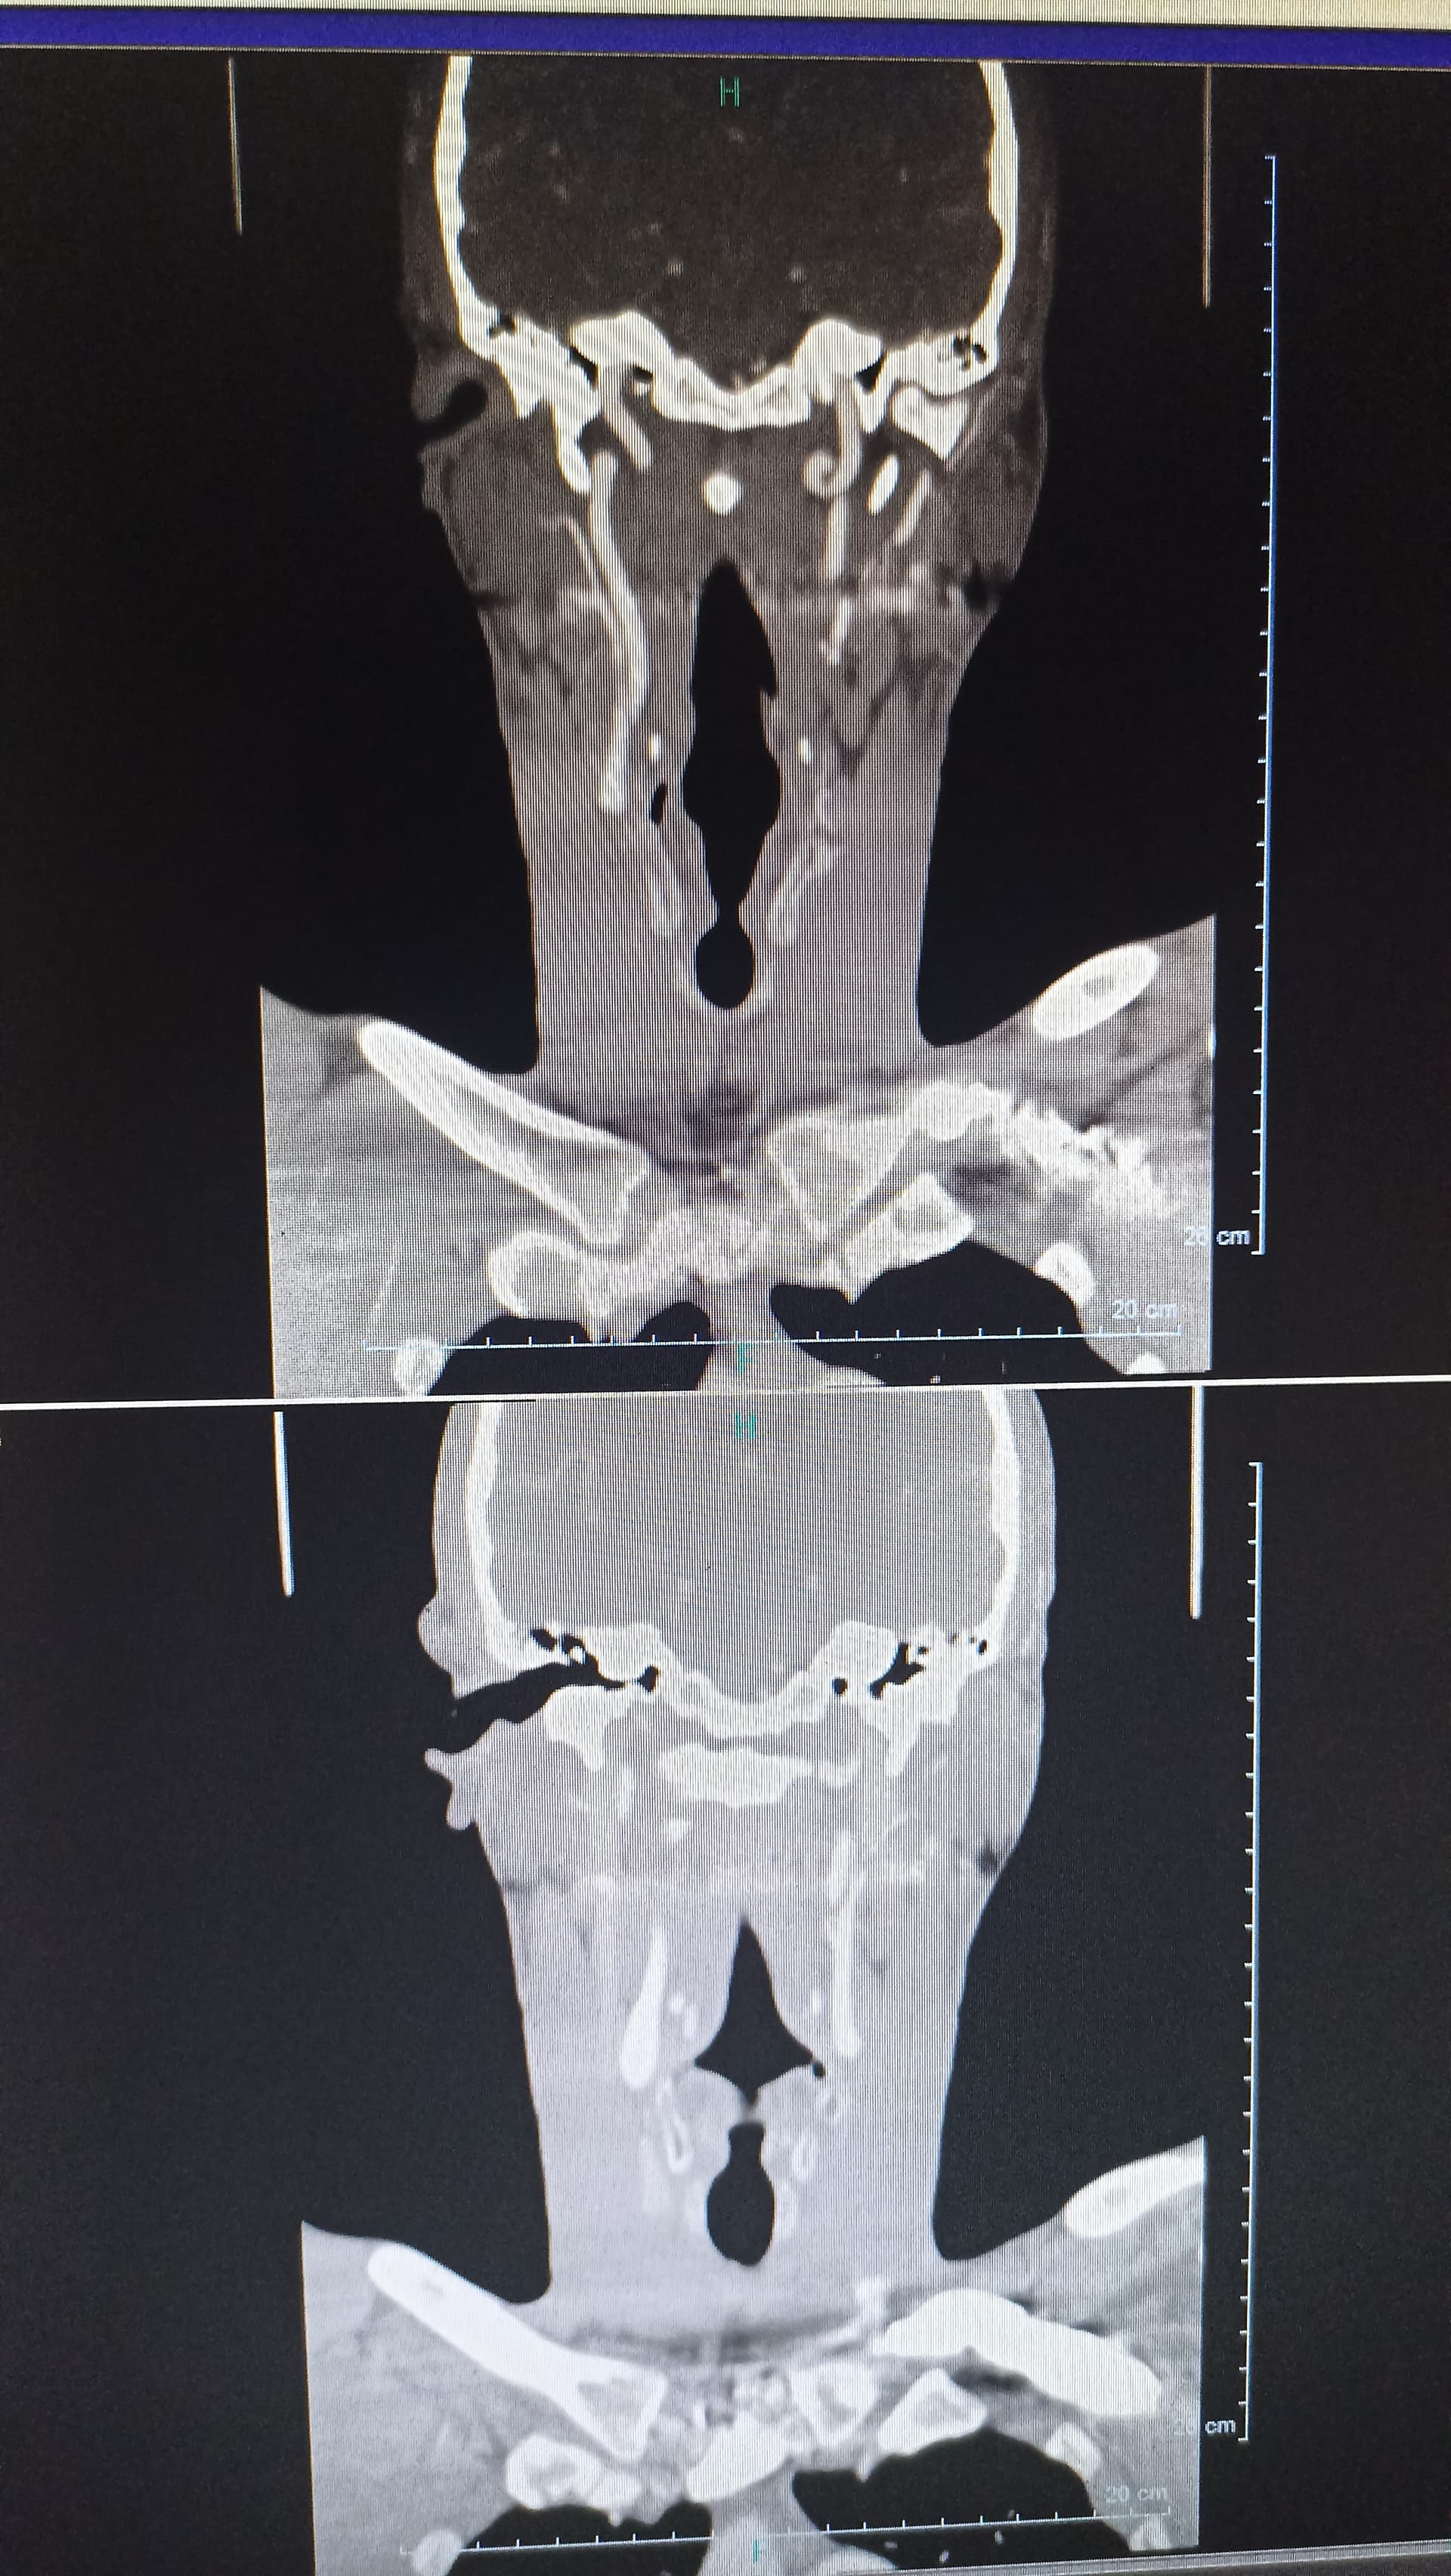

First time having a go at this and I can’t see the veins properly or ligaments one styloid looks to be at a complete different angle to the other and going behind the jaw

I did comment on your other post as well… you can’t see the veins at all as this is a regular CT, not the contrast one. The left side especially is very angled, they’re both quite wide at the top so could be compressing nerves at the skull base. The left side looks like there’s a decent space between the styloid & C1 space so less likely to cause IJV compression, I can’t tell with the right. You can only see the stylo-hyoid ligaments if they’re calcified, yours aren’t, so that’s good. The hyoid bone processes do look quite long though, that can sometimes cause issues.

Hopefully these images can give a better view

They do look extremely thick to me compared to many others I’ve seen on here

Regarding your styloids, both look thick at the top & very angled. The tip of the right one looks very pointed. I can’t see the tip of the left one. They don’t look super long but the angle & thickness could definitely be plying into your symptoms.